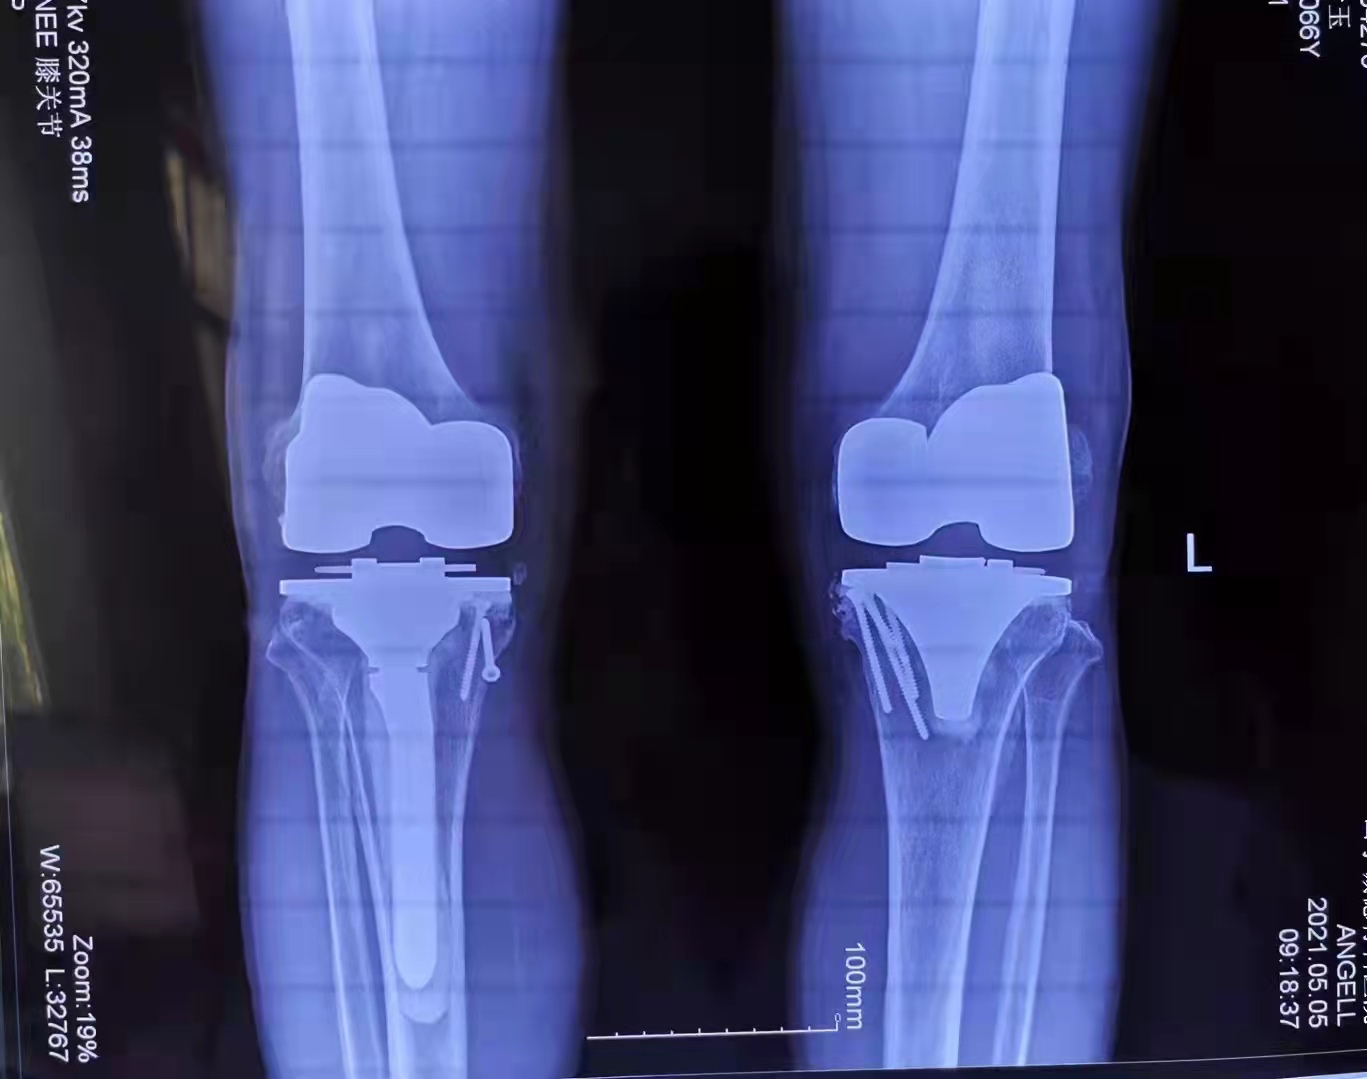

他來到了山亭誠(chéng)德骨科醫(yī)院醫(yī)治,多年的頑疾。讓馬先生本沒抱有任何希望,然而,誠(chéng)德骨科醫(yī)院的李俊鋒院長(zhǎng)及團(tuán)隊(duì)給他帶來了希望,對(duì)這種復(fù)雜的病情進(jìn)行了精心的會(huì)診,制定了詳細(xì)而縝密的手術(shù)方案,予以分期進(jìn)行雙側(cè)膝關(guān)節(jié)置換手術(shù)。

手術(shù)恢復(fù)非常讓人滿意,馬先生已經(jīng)像正常人一樣參加工作,過上了幸福愉快的生活。